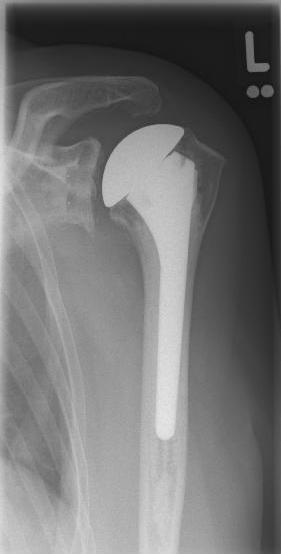

Conventional stem prostheses for omarthrosis and acetabular wear

right: anatomical shoulder prosthesis with glenoid replacement (Affinis type, Mathys company)

left: X-ray image of a short-shaft prosthesis

right: Short-shaft prosthesis (Affinis Short type, Mathys company)